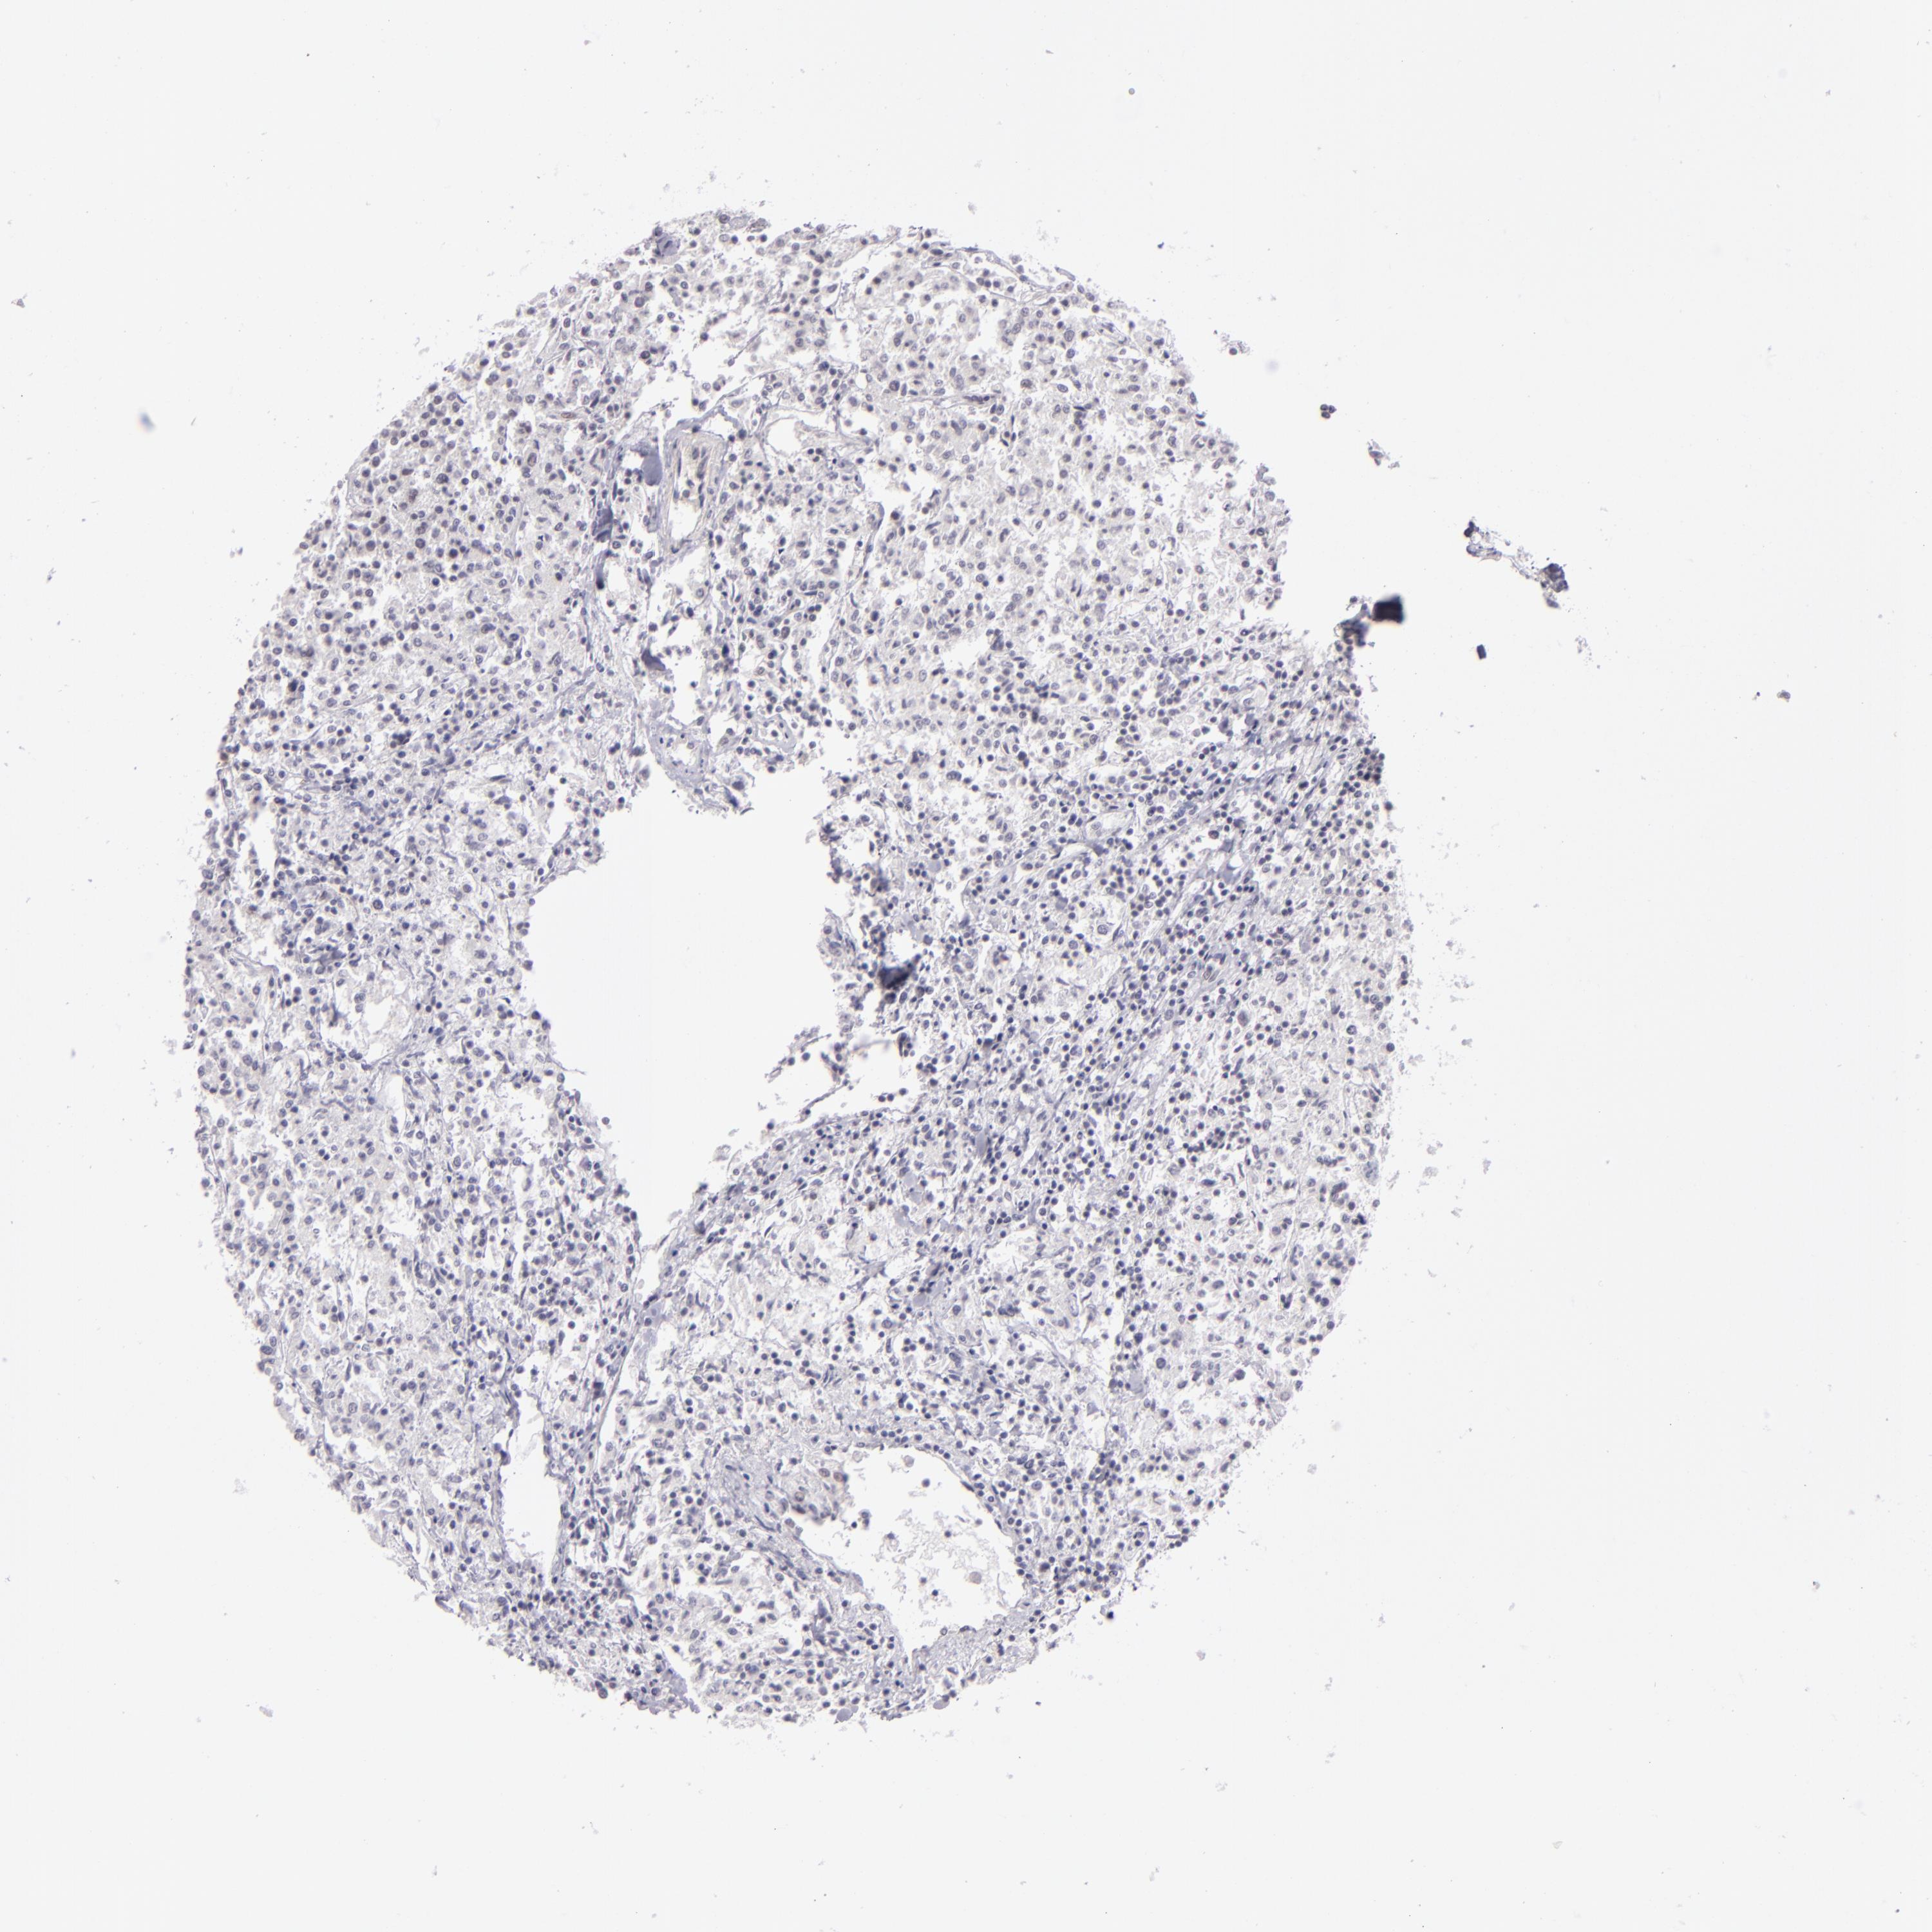

LYMPHOMA - Protein expressioni

A mouse-over function shows sample information and annotation data. Click on an image to view it in a full screen mode. Samples can be filtered based on level of antibody staining by selecting one or several of the following categories: high, medium, low and not detected. The assay and annotation is described here.

Each image is clickable and will lead to virtual microscopy that enables deeper exploration of all samples and also displays staining intensity scores, fraction scores and subcellular localization as well as patient and tissue information for each sample.

Antibody HPA001791

Staining

Medium

Intensity

Moderate

Quantity

75%-25%

Location

Nuclear

Malignant lymphoma, non-Hodgkin's type, High grade

Hodgkin's disease, NOS

Malignant lymphoma, non-Hodgkin's type, Low grade